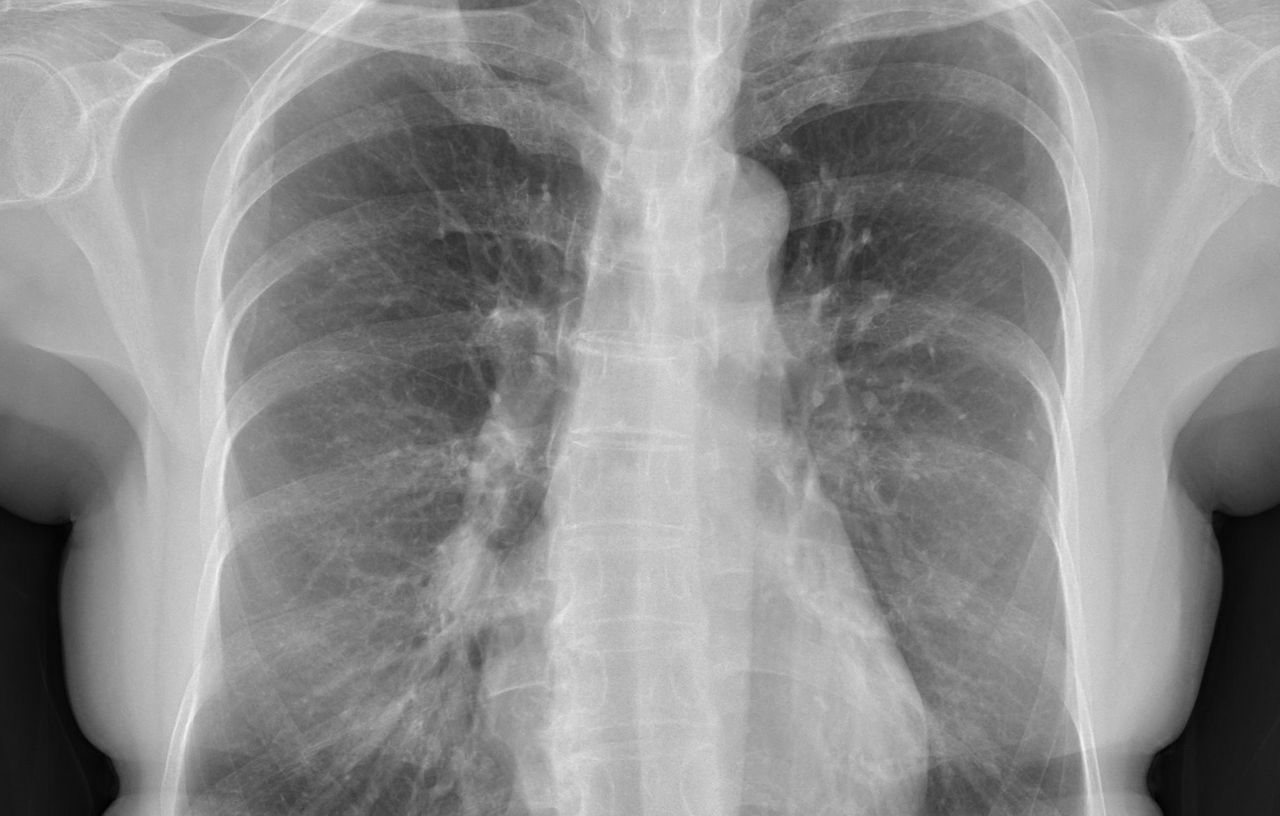

▲醫師說,X光片有問題,「讓大家找看看在哪裡」。(圖/翻攝蘇一峰臉書)

蘇一峰指出,X光一照看完覺得有問題,「讓大家找看看在哪裡」;安排後續的電腦斷層CT檢查,發現是3公分的肺癌,大概第二期或三期。